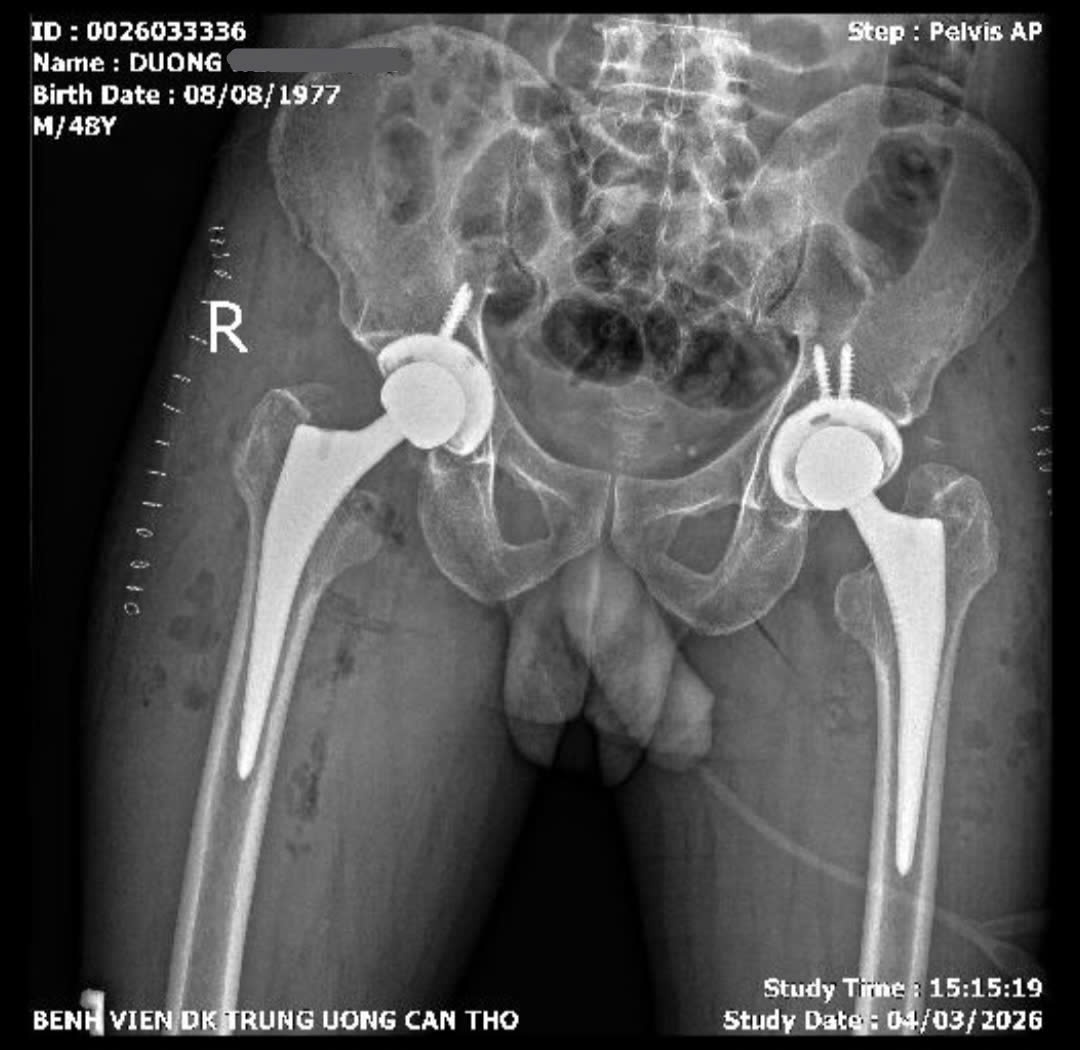

Ngày 10/3, Bệnh viện đa khoa Trung ương Cần Thơ cho biết, các bác sĩ vừa thực hiện thành công ca phẫu thuật thay khớp háng hai bên, trong cùng một lần mổ bằng đường mổ trực tiếp phía trước cho bệnh nhân bị hoại tử chỏm xương đùi hai bên. Nhờ áp dụng kỹ thuật ít xâm lấn, bệnh nhân có thể tập đi chỉ sau 2 ngày, mở ra nhiều cơ hội phục hồi sớm cho người mắc bệnh lý khớp háng nặng.

Bệnh nhân Dương H. P. (SN 1977, ngụ TP Cần Thơ), nhập viện trong tình trạng đau khớp háng hai bên kéo dài nhiều năm, đặc biệt tăng nhiều trong khoảng 6 tháng gần đây, phải thường xuyên sử dụng thuốc giảm đau và gặp khó khăn khi đi lại.

Qua thăm khám và các xét nghiệm hình ảnh, các bác sĩ xác định bệnh nhân bị hoại tử chỏm xương đùi hai bên – một bệnh lý nguy hiểm của khớp háng, do giảm hoặc mất nguồn máu nuôi chỏm xương đùi, dẫn đến hoại tử xương, đau kéo dài và có thể gây xẹp khớp nếu không điều trị kịp thời. Bệnh nhân được chỉ định phẫu thuật.

Các bác sĩ đã lựa chọn đường mổ trực tiếp phía trước – phương pháp phẫu thuật ít xâm lấn trong thay khớp háng. Ca mổ kéo dài khoảng 4 giờ, tiến hành thay khớp háng hai bên trong cùng một lần phẫu thuật.

Sau phẫu thuật, bệnh nhân phục hồi thuận lợi và đến ngày thứ 2 đã có thể tập đi lại với khung hỗ trợ và tự đi không cần dụng cụ hỗ trợ; dự kiến ra viện sau 5 ngày.